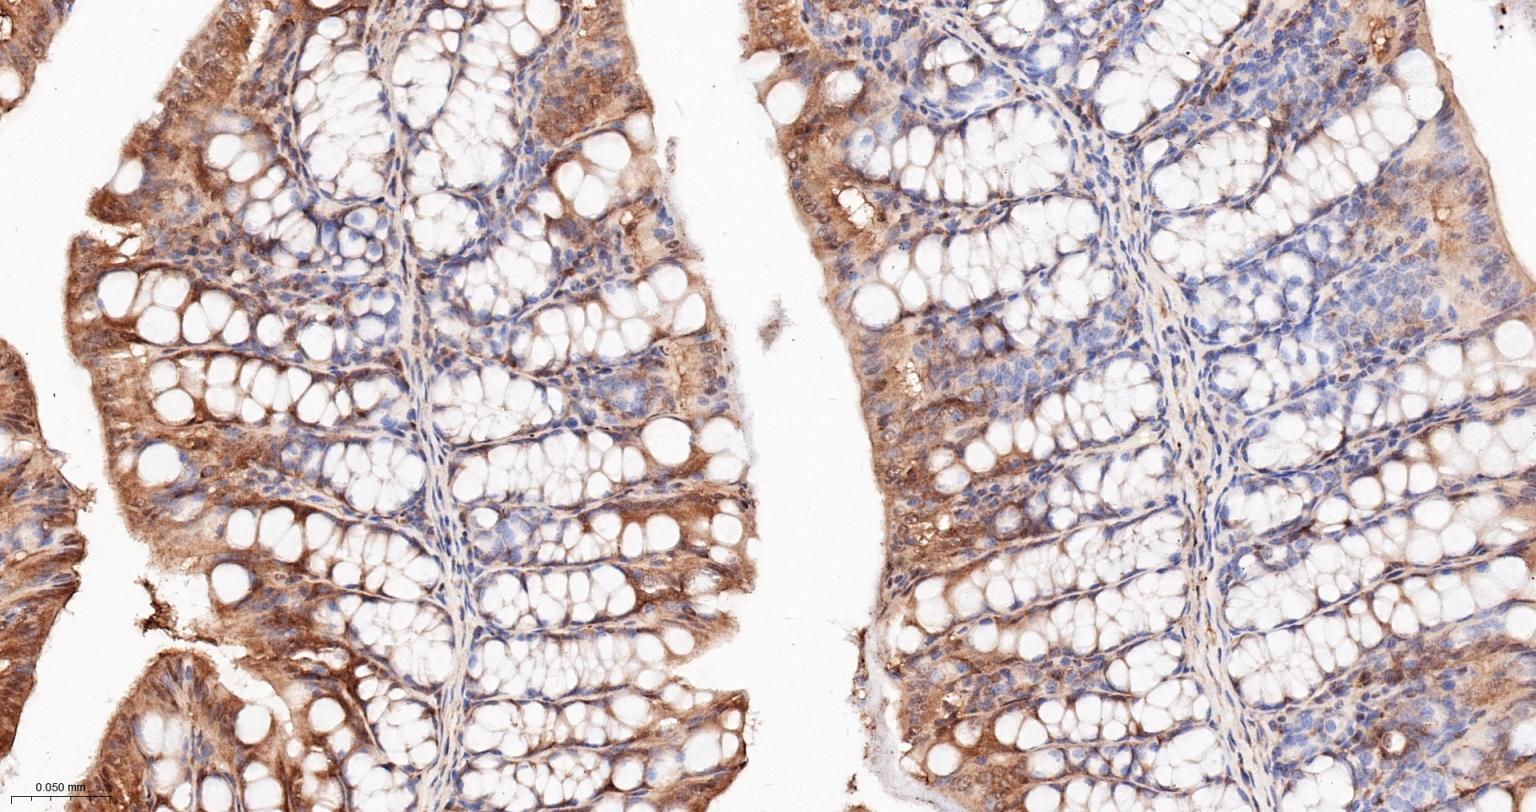

Paraformaldehyde-fixed, paraffin embedded Rat Colon; Antigen retrieval by boiling in sodium citrate buffer (pH6.0) for 15 min; Antibody incubation with Hsp90 alpha Monoclonal Antibody, Unconjugated(bsm-52353R) at 1:200 overnight at 4°C, followed by conjugation to the SP Kit (Rabbit, SP-0023) and DAB (C-0010) staining.

Paraformaldehyde-fixed, paraffin embedded Mouse Colon; Antigen retrieval by boiling in sodium citrate buffer (pH6.0) for 15 min; Antibody incubation with Hsp90 alpha Monoclonal Antibody, Unconjugated(bsm-52353R) at 1:200 overnight at 4°C, followed by conjugation to the SP Kit (Rabbit, SP-0023) and DAB (C-0010) staining.